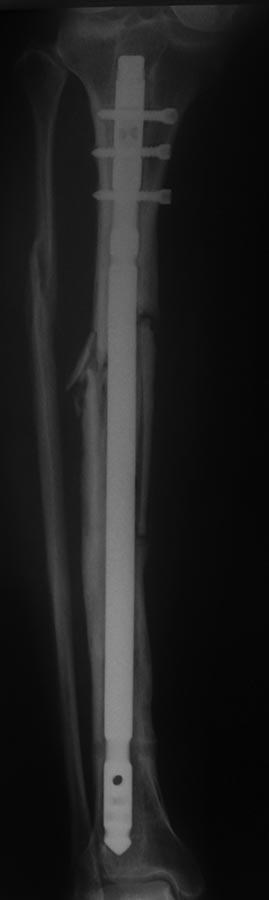

Добрый вечер. Прошу ваше мнения по данному случаю. Поступила Пациентка

50 лет, жительница села. В 18.12.2012 г. в пьяном угаре оступилось о

порог двери, после чего поступает в отделение с переломом голени

(первоначальных снимков нет). 19.12.2012 г. был выполнен

закрытый БИОС, благополучно выписана с рекомендациями. На назначенное

время не явилось.

Пришла в 26.02.2013 г., где удалили 2 блокирующих винта и в 20.05.2013

г. тоже убрали 2 блокирующих винта. Также благополучно потерялось,

появилось в октябре 2014 г., с признаками не сращения правой

большеберцовой кости. После чего был выполнен реостесинтез

штифтом. На данный момент беспокоит боль в области коленного,

голеностопного суставов и средней трети голени, отек голени. Как быть

дальше????